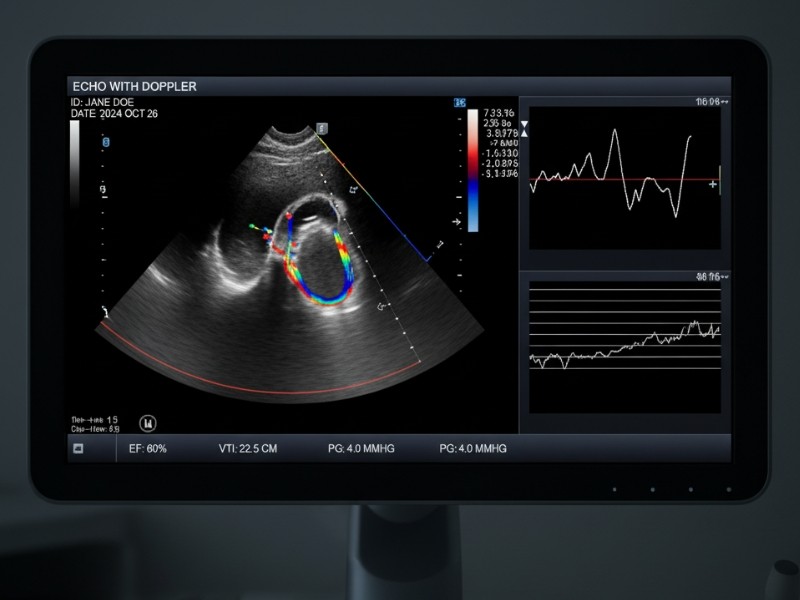

Exame não invasivo e sem radiação que utiliza ultrassom de alta frequência para visualizar em tempo real as estruturas do coração — câmaras, válvulas, paredes e fluxo sanguíneo — com análise Doppler da velocidade e direção do sangue nas artérias e válvulas. Na CLIMT, o ecocardiograma é realizado por cardiologistas com certificação em ecocardiografia, em equipamentos digitais de última geração, com laudos emitidos no mesmo dia ou em até 24 horas úteis. Desde 1995 referência em diagnóstico cardiovascular em Goiânia, atendendo pacientes particulares, convênios e programas de saúde ocupacional.

O exame não requer preparo especial — sem jejum e sem suspensão de medicamentos. O paciente deita em decúbito lateral sobre a maca e o cardiologista aplica gel condutor sobre o tórax, movimentando o transdutor em diferentes posições (janelas ecocardiográficas) para obter imagens de todas as estruturas cardíacas. O sistema exibe em tempo real o funcionamento das câmaras, válvulas e grandes vasos, com sobreposição colorida do fluxo sanguíneo pela análise Doppler.

O exame tem duração média de 30 a 40 minutos. Ao final, o cardiologista emite laudo detalhado com medições das câmaras, fração de ejeção, avaliação de cada válvula, pressão pulmonar estimada e interpretação clínica conclusiva — com imagens digitais. O resultado é entregue no mesmo dia ou em até 24 horas úteis.